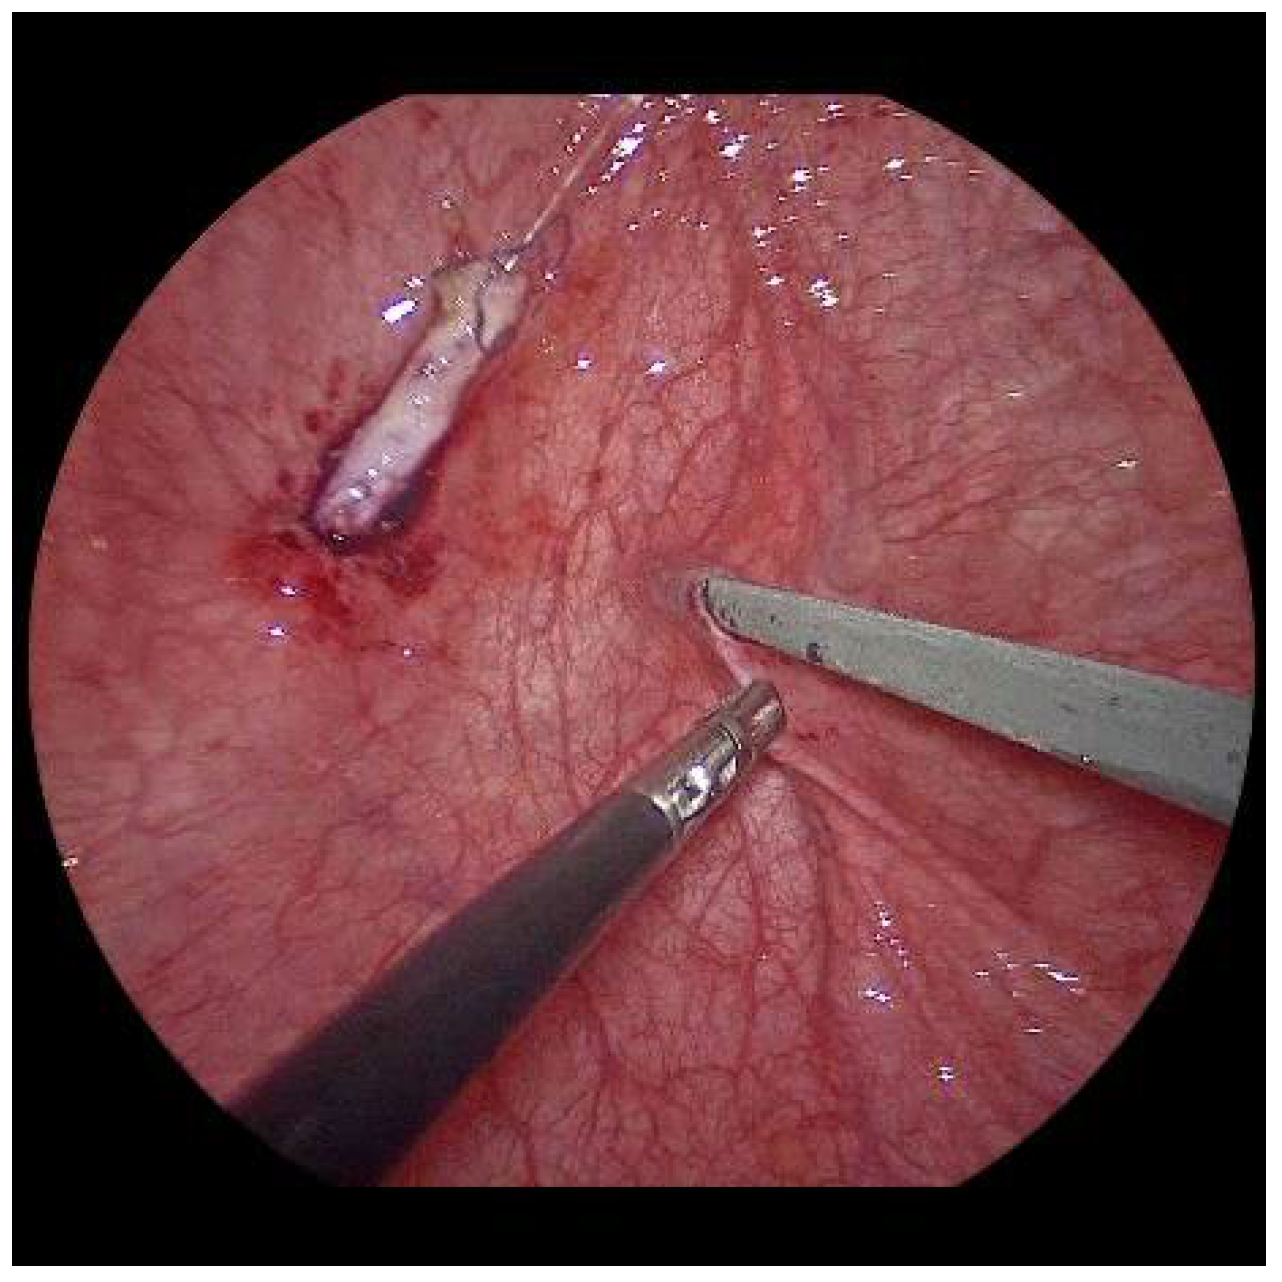

Submucosal tunnel preparation using curved scissors often requires some patience. When the tunnel is finished, the refluxive ureters are now shifted to the opposite side equivalent to the open approach. An ipsilateral suture fixes the ureter to the detrusor (Figure 6).

Figure 6.

To reduce the tension on the neoostium, the ureter is pexed at the bladder entrance.